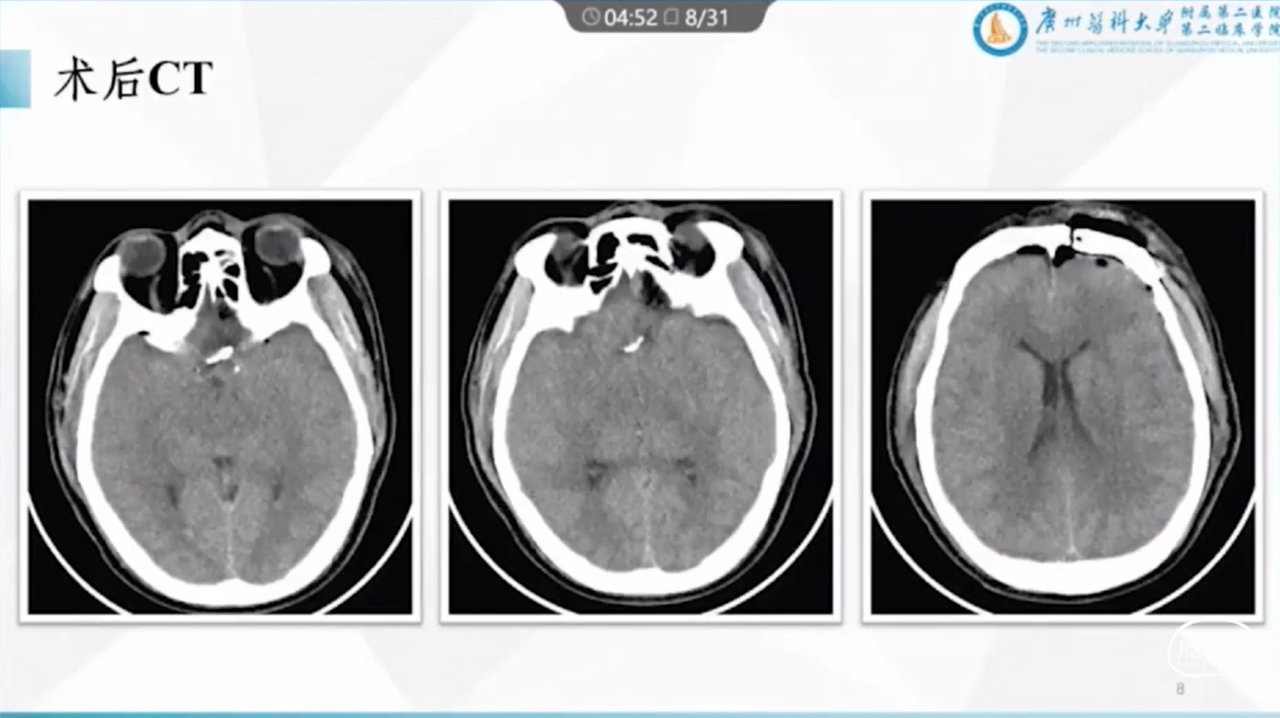

王业忠教授:眉弓锁孔前交通动脉瘤术中破裂的处理对策